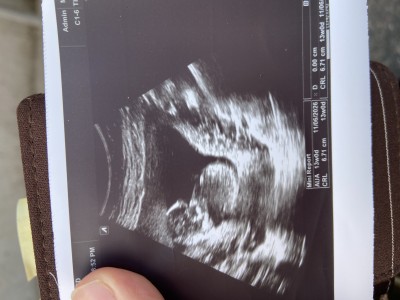

Kızlar doktor emin olamadı erkek bence dedi ama net değil kordon da olabilir ona benziyo dedi ben oğlumu bu haftada net öğrenmiştim aynı doktor du ama bu sefer böyle oldu kız mıdır acaba

Gebelik haftası 13

Ben hiç anlamıyorum belki anlarsınız diye attım ama doktor erkek bence dedi kordon da olabilir dedi oğlumda 13 haftalıkta yüzde yüz erkek demişti

Biraz karışık ama bu haftalar daha çok erken

Bana kız gibi geldi